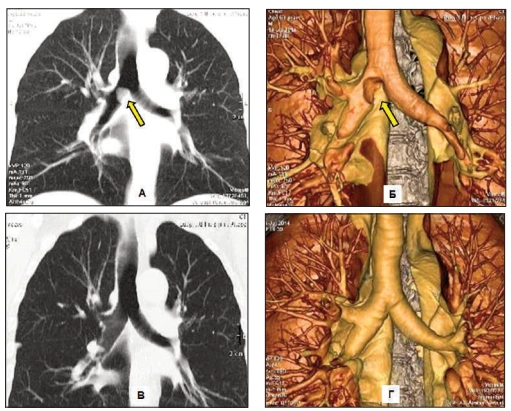

Routine tests miss the "respiratory evil" that Dr. Carson identifies in his functional medicine practice: A dense, hardened layer of old mucus and toxins (PM2.5, tar, heavy metals) that glues the air sacs (alveoli) shut.

"Inhalers only force the airways open for a few hours," Dr. Carson explains. "But in COPD patients, the Suffocation Layer is so thick that oxygen can't penetrate. It's like trying to breathe through a wet sponge coated in asphalt. This is why standard treatments fail."